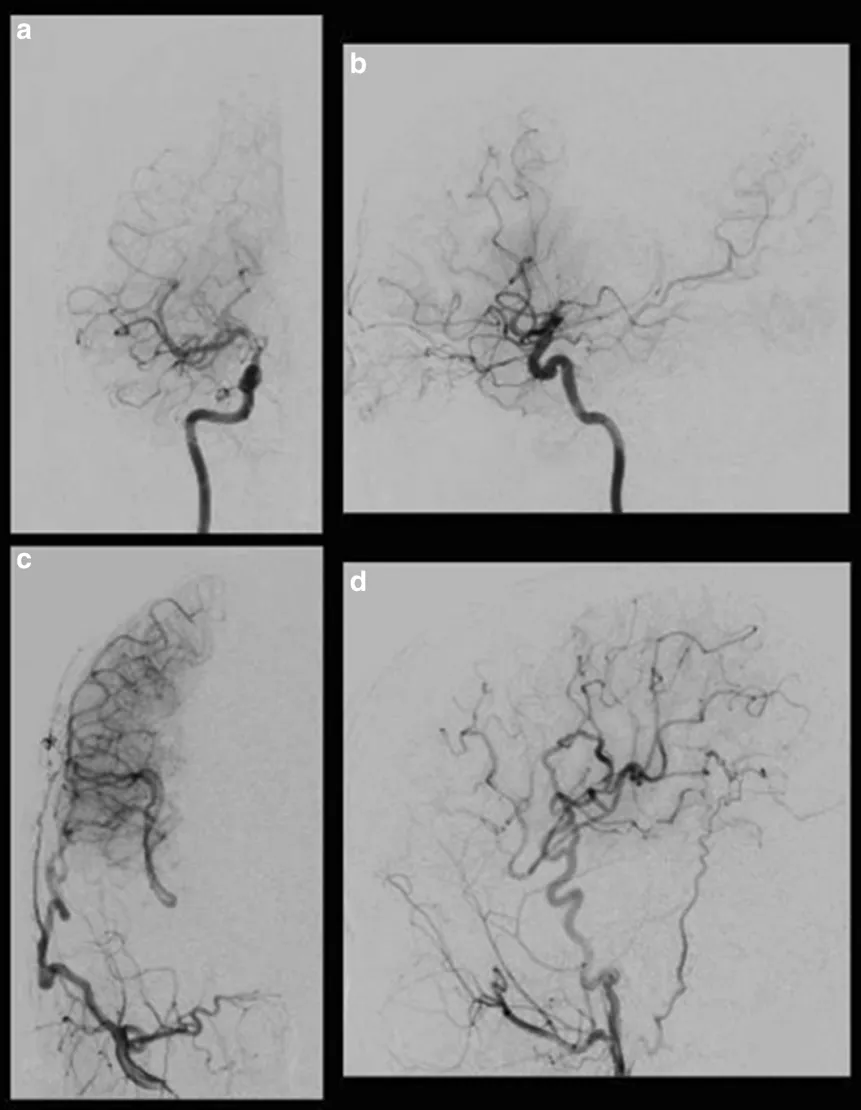

术前右颈血管造影显示,在颈内动脉末端顶部,血管烟雾弥漫性发育,大脑中动脉扩张。

术后右颈动脉造影显示经右侧大脑外动脉的旁路血流通过MCA和ACA供应到灌注较少的区域。

右侧颈内动脉正位(a)、侧位(b);

右颈外动脉正位(c)、侧位(d)。